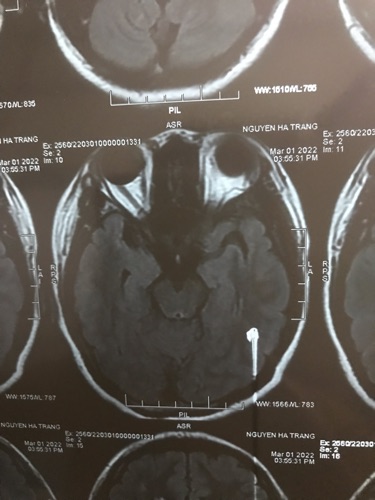

Em chào các bác sĩ ạ. Nay em có đi khám về hậu covid do thường xuyên mất ngủ , khó thở thì được bác sĩ khám nội phát hiện ra hình ảnh chụp MRI có tổn thương nghi ngờ viêm não nhưng do không phải chuyên môn nên bác sĩ khuyên em nên khám chuyên khoa thần kinh, khả năng cao chỗ viêm có từ trước khi em bị covid Em cần nhờ bác sĩ bên mình khoa thần kinh xem giúp em với ạ và nếu khám thì khám viện nào tại HN được ạ. Em cảm ơn ai